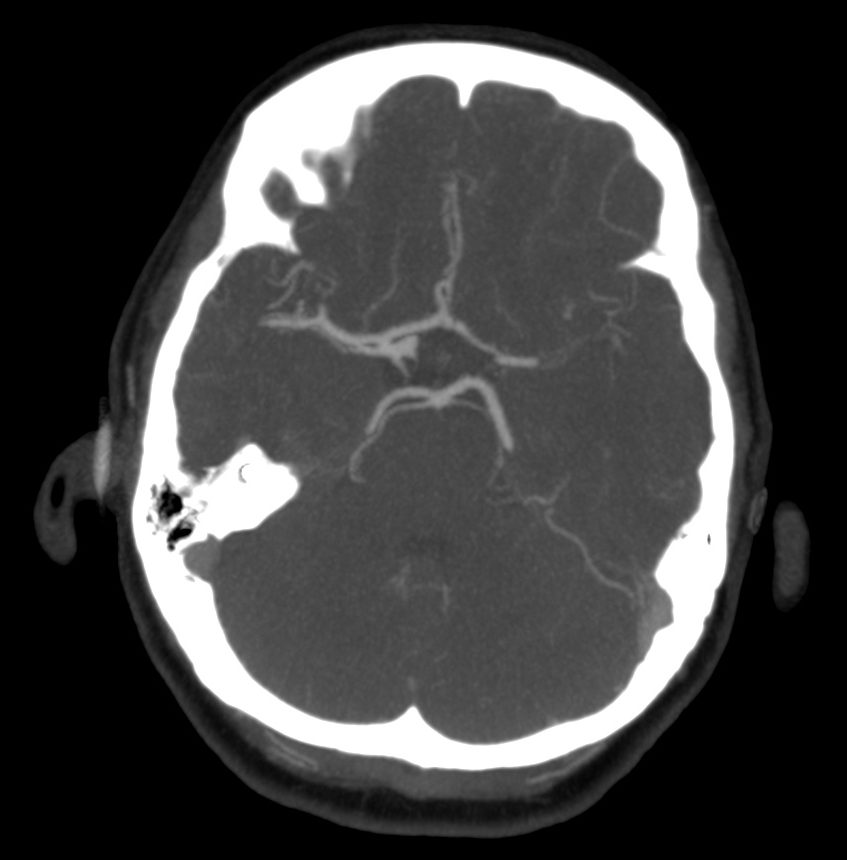

ANGIOGRAFÍA TC.

Sirve para:

- Definir el lugar de oclusión.

- Descartar disección arterial.

- Grado de colateralidad.

- Grado de arterioesclerosis.

Con la información aportada podremos pronosticar mejor la localización y extensión del infarto. Además, proporciona un mapa vascular para el tratamiento endovascular.

b) Estudio:

- MIP de 25mm en Polígono, con reconstrucciones en planos básicos.

- Reformateo curvo para vasos cervicales (segmento cervical de las carótidas, arterias vertebrales)

c) Objetivo:

Es importante leer el estudio orientados por la clínica y los hallazgos de la TC sin contraste. Aún así, es conveniente seguir una sistemática para estudiar todos los vasos importantes y no pasar por alto la patología.

La angioTC nos sirve para:

- Detectar trombosis: informar acerca de la apariencia, localización, dimensiones. Localizaciones frecuentes:

- Tándem ACI-ACMedia

- Tronco Basilar

- Región carotídea.

- Segmento M1 de ACM

- Segmento M2 de ACM

- Estudiar morfología del cayado y variantes + descartar estenosis en bifurcaciones carotídea. Datos muy importantes de cara para el intervencionismo.

- Detectar disección arterial (produce ictus por suelta de embolos o por oculisón hemodinámica)

- Valoración de Polígono de Willis: patología (estenosis, aneurismas, malformaciones) y sus variantes de la normalidad (informar de la existencia de comunicantes, dominancia, ACoP de origen fetal, etc…)

- No olvidar repasar el parénquima cerebral para definir mejor el parénquima isquémico.